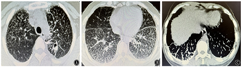

患者女,35岁,因"体检发现肺部病灶8年,咯血半个月"于2022年9月9日入院。患者8年前体检行胸部CT检查发现双肺弥漫结节影(图1);2014年10月28日在当地医院完善气管镜检查、肺功能检查,均未见明显异常;后行肺穿刺术,术后病理为大部分血块、皮肤纤维、横纹肌细胞,见少量钙化。未予以治疗。2022年8月20日患者在家中突发咯血1次,量约10 ml,颜色鲜红,后未再出现咯血。2022年9月3日患者查胸部CT提示双肺弥漫性病变,双侧胸膜增厚伴钙化,左上肺结节伴空洞(图2)。左上肺结节及空洞为新发病灶。为进一步诊治,于2022年9月9日收住南京中医药大学附属南京医院结核科。既往史:患者既往身体健康,否认结核病史,否认高血压、心脏病、糖尿病、脑血管病及精神疾病,从事足浴店服务员工作,否认粉尘接触史,否认有疫水、疫源接触史,否认冶游史,否认吸烟、饮酒史,否认食物、药物过敏史,家族中姐姐曾体检发现双肺弥漫性病灶,未进一步检查,父母为表兄妹近亲结婚。入院体检:体温36.4 ℃,心率80次/min,呼吸18次/min,血压124/85 mmHg(1 mmHg=0.133 kPa)。患者意识清楚,精神良好,口唇无发绀,浅表淋巴结未触及肿大,双肺呼吸音清,未闻及干湿性啰音,四肢关节无异常,无杵状指,体格检查未见其他异常。实验室检查:血尿粪常规、血生化、凝血功能、自身抗体、血沉、血肿瘤标志物、血清血管紧张素转化酶均正常;血抗结核抗体阴性,血清γ-干扰素释放试验阳性,结核菌素试验强阳性;3次痰涂片找抗酸杆菌阴性,痰普通菌、真菌培养阴性,痰脱落细胞检查未找到肿瘤细胞。入院诊断为"继发性肺结核,双肺弥漫性病灶待查"。患者除咯血外,无明显其他症状,入院后完善甲状腺超声、泌尿系彩色超声、腹部CT,均未见明显异常,心脏彩色超声提示心内结构未见明显异常,左室收缩功能正常范围。为明确诊断,行支气管镜检查,术中可见左肺上叶后段开口轻度狭窄,黏膜粗糙水肿,于此处用60 ml生理盐水冲洗,留取灌洗液送检,左肺下叶基底段见色素沉着,开口未见明显狭窄,右肺上叶可见色素沉着,见可疑黑色丝状物,予以吸出。灌洗液涂片找抗酸杆菌阴性,灌洗液结核分枝杆菌DNA<500 copies/ml,灌洗液送检GeneXpert MTB/RIF结核分枝杆菌检测阳性,灌洗液送检结核分枝杆菌靶向高通量基因测序检测出结核分枝杆菌复合群,序列数为18。肺结核诊断成立。考虑到患者父母有近亲结婚家族史,姐姐有类似肺部病灶,影像表现为双肺弥漫性病变和胸膜下多发钙化灶,后行外周血基因分析(表1)检查,提示SLC34A2基因11号外显子纯合子突变(c.1267G>A)。综合分析,患者影像表现为双肺弥漫病灶伴胸膜下片状钙化,左上肺结节伴空洞。结合患者家族史、住院期间相关检查结果以及基因分析结果,考虑诊断为"PAM合并肺结核"。给予异烟肼、利福平、吡嗪酰胺、乙胺丁醇抗结核治疗,定期随访。1个月后复查胸部CT(图3)提示左上肺病灶较前略吸收,其余病灶未见明显改变。

PAM因为症状不典型,在诊断时多依靠影像学检查,同时结合肺活检病理及相关家族史。临床上也可以进行分子遗传学检查来进行诊断。本例患者有明确的家族史,其父母为表兄妹近亲结婚,姐姐体检时也发现双肺弥漫病灶。患者8年前的影像表现为双肺弥漫性病变,可见"火焰征",即胸膜下多发片状钙化影,符合PAM影像表现。肺穿刺病理结果可见部分钙化,符合PAM的病理学改变。分子遗传学检查提示SLC34A2基因11号外显子纯合子突变,单纯该基因型突变导致PAM为首次在亚洲人群中发现,既往有国外文献报道过第11外显子突变引起PAM的案例[12];在国内案例报道中,也有第8个外显纯合子突变合并第11个外显子突变的案例,突变位点均为1267G>A(P.Gly423Arg),并且在本案例中通过蛋白功能预测软件分析提示该位点为有害突变。因此,高度怀疑此突变与PAM发病相关。考虑PAM可能性大。同时,患者肺泡灌洗液GeneXpert MTB/RIF结核分枝杆菌检测阳性,该项检查对结核分枝杆菌感染的敏感度高于涂片及培养,特异度可达98%~100%[13]。临床中可以通过Genexpert MTB/RIF与涂片或胸部CT检查结合,用于诊断疑似的肺结核患者。根据我国《结核病病原学分子诊断专家共识》[14],当分子生物学检测结果阳性、细菌学检测阴性时,应以分子生物学检测结果为准,视为结核分枝杆菌阳性。同时灌洗液送检结核分枝杆菌靶向高通量基因测序提示检测出结核分枝杆菌复合群,序列数为18,进一步证实了肺结核诊断。经过抗结核治疗后,患者左上肺病灶较前吸收,综合考虑判断该患者为PAM合并肺结核。不过在本案例中,患者父母有近亲结婚史,姐姐有类似胸部影像表现,但未能获得患者父母及姐姐的相关临床资料,无法确定其家系SLC34A2基因的遗传特征。本例报道的SLC34A2基因11号外显子纯合子突变(c.1267G>A)为首次在亚洲人发现的第11外显子的核苷酸突变,通过蛋白功能预测软件REVEL预测为有害突变,高度怀疑此突变与PAM发病相关,但仍需进一步研究证实。

PAM在胸部CT上主要表现为稀薄化的弥漫性磨玻璃影、密度较高的粟粒状结节、胸膜下小结节、胸膜下线性钙化("白描征")、胸膜下片状钙化影("火焰征")、结节性钙化、沿小叶间隔的钙化等[15]。在临床上需要与尘肺、血行播散型肺结核、结节病、肺泡蛋白沉积症等疾病鉴别。急性血行播散型肺结核CT影像表现为两肺广泛均匀分布粟粒大小的结节状密度增高影,特点为"三均匀",即病灶分布均匀、大小均匀和密度均匀。而亚急性血行播散型肺结核"三均匀"特征不明显,可表现为新旧病灶共存,可夹杂斑片状、结节状阴影,可伴坏死和空洞。PAM虽然也可以表现为双肺多发粟粒状结节影,但往往结节密度高,分布不均匀,往往伴有自上而下增多的特点,多伴有胸膜下钙化[16]。在本例中,患者胸部CT除双肺弥漫结节影外同时合并左肺上叶尖后段实性结节影,可见空泡及毛刺,除考虑肺结核外,还需要同肺癌、肺脓肿、肺放线菌病、血管炎、肺梗死等疾病相鉴别。肺结核引起的空洞型病灶以薄壁多见,周围常有卫星灶,可伴粗长毛刺或受纤维牵拉而导致空洞形态不规则,肺癌引起的空洞一般为厚壁,内缘凹凸不平,有壁结节,肿块周围伴有毛刺。上述疾病在影像表现上具有相似之处。当仅凭影像学无法确诊时,需要依赖病原学、病理学、免疫学等相关检查加以鉴别。